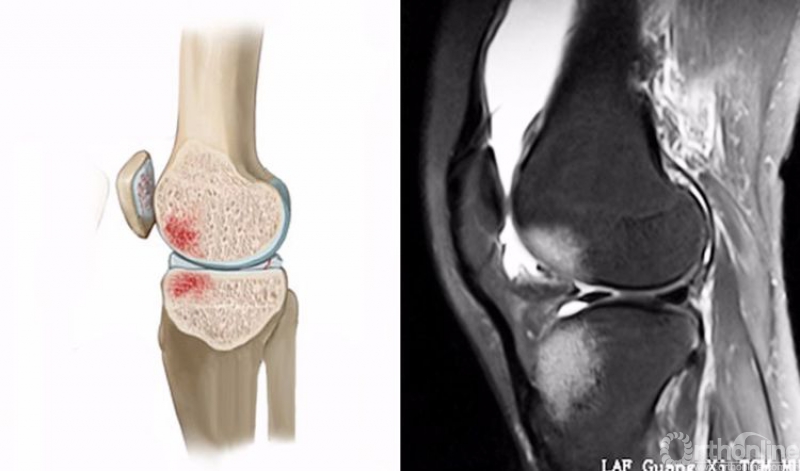

1.轴移损伤(pivot-shift injury)

膝关节在不同程度的屈曲和胫骨外旋或股骨内旋状态下,受到外翻力的作用。通常在快速减速并改变方向的时侯发生前交叉韧带(ACL)撕裂,一旦ACL撕裂,胫骨就相对于股骨前移,使股骨外侧髁和胫骨外后方撞击。其屈曲的程度决定股骨髁挫伤的部位。

膝关节轴移损伤在MRI上主要表现为股骨外侧髁和胫骨外后方骨髓水肿,T2WI及STIR像呈高信号改变,一般预示着ACL损伤。